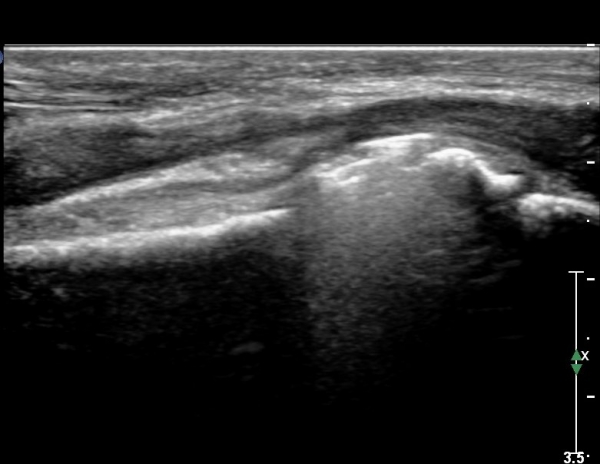

ŽÃËÀÚ¸¦ Á¶±Ý ¸»´ÜÀ¸·Î À̵¿ÇÏ´Ï FPL Å©±â°¡ ±Þ°ÝÈ÷ °¨¼ÒÇÔ. FCR,  FDP ÁÖº¯ ¹Ì¼¼ÇÑ ¼ö¾×Àú·ù °üÂûµÊ(»çÁø4, 5)

ŽÃËÀÚ¸¦ Á¶±Ý ´õ ¸»´ÜÀ¸·Î À̵¿ÇÏ´Ï FCR¿Í FDP »çÀÌ¿¡¼­ Àú¿¡ÄÚ »óÅÂÀÇ FPL °¡ °üÂûµÇ°í °íÁ¤¹°¿¡ ÀÇÇÑ

¾Ð¹ÚÀÌ °üÂûµÊ(»çÁø 6, 7)